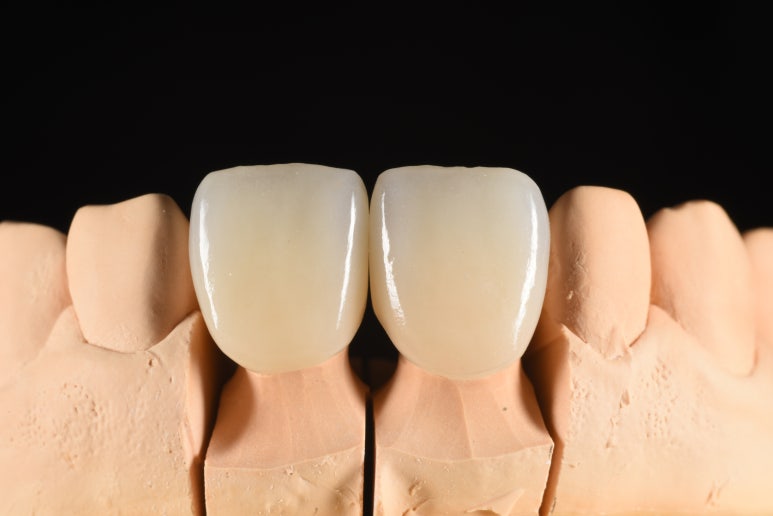

크라운 제작과정

완성된 크라운